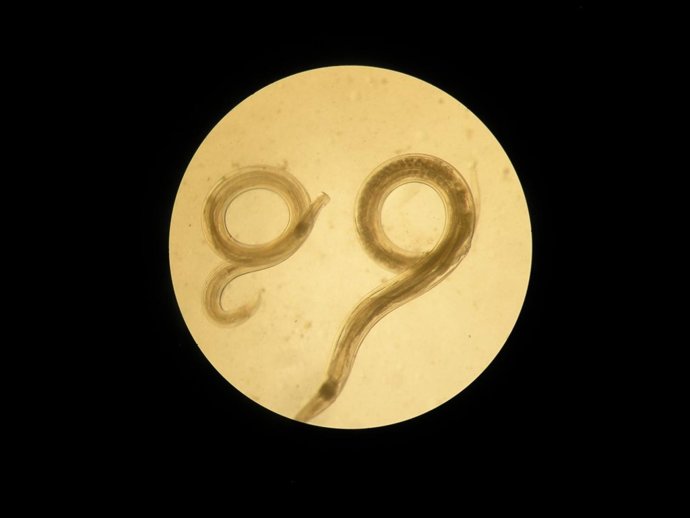

Vista al microscopio del gusano Aspiculuris,

La investigación, liderada por la Universidad de Granada y en la que han participado por parte de la Universitat de València M. Dolores Bernal del Departamento de Bioquímica y Biología Molecular y A. Bolado-Ortiz y María Trelis del Departamento de Farmacia y Tecnología Farmacéutica y Parasitología ha utilizado como modelo el gusano Aspiculuris, un parásito intestinal, presente en ratones, similar a los oxiuros humanos.